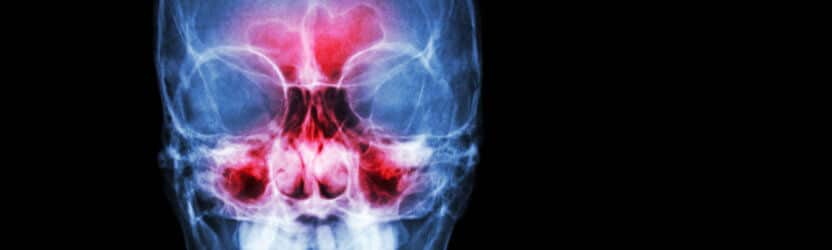

סינוסיטיס הוא דווקא לא מקרה של דלקת מערות האף שהיא בכלל כאב שיניים, אלא להפך – כאב השיניים הוא תסמין של הדלקת עצמה. סינוסיטיס היא דלקת אשר מקורה בחללי אוויר גדולים בעצמות הגולגולת. הדלקת מאופיינת בתסמינים כמו גודש באף, ריח רע מחלל הפה וכאב פנים ספציפי באיזור הסינוס המזוהם, אשר נוטה להתגבר בשינוי של מנח הראש. עקב הקרבה של הסינוסים לשיניים האחוריות בלסת העליונה, לא אחת מאבחנים דווקא את הסינוסיטיס אבחון מוטעה של כאב שיניים.